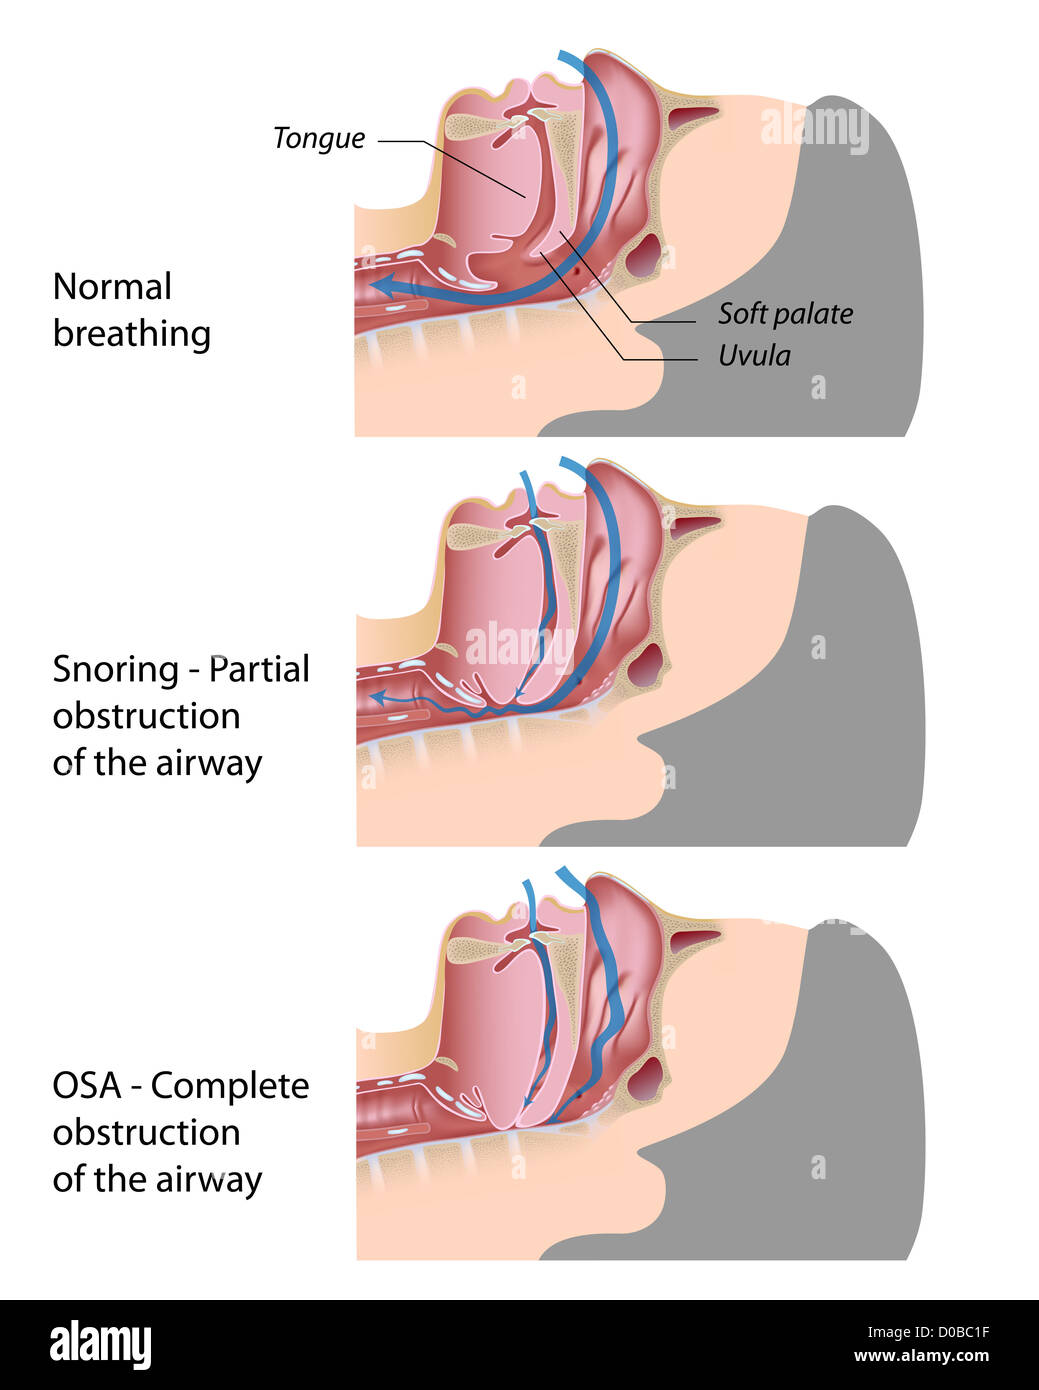

Snoring and sleep apnea Stock Photohttps://www.alamy.com/image-license-details/?v=1https://www.alamy.com/stock-photo-snoring-and-sleep-apnea-51882027.html

Snoring and sleep apnea Stock Photohttps://www.alamy.com/image-license-details/?v=1https://www.alamy.com/stock-photo-snoring-and-sleep-apnea-51882027.htmlRFD0BC1F–Snoring and sleep apnea

Upper airway human anatomy in normal sleeping and have snoring. Stock Vectorhttps://www.alamy.com/image-license-details/?v=1https://www.alamy.com/stock-photo-upper-airway-human-anatomy-in-normal-sleeping-and-have-snoring-98953575.html

Upper airway human anatomy in normal sleeping and have snoring. Stock Vectorhttps://www.alamy.com/image-license-details/?v=1https://www.alamy.com/stock-photo-upper-airway-human-anatomy-in-normal-sleeping-and-have-snoring-98953575.htmlRFFMYM87–Upper airway human anatomy in normal sleeping and have snoring.